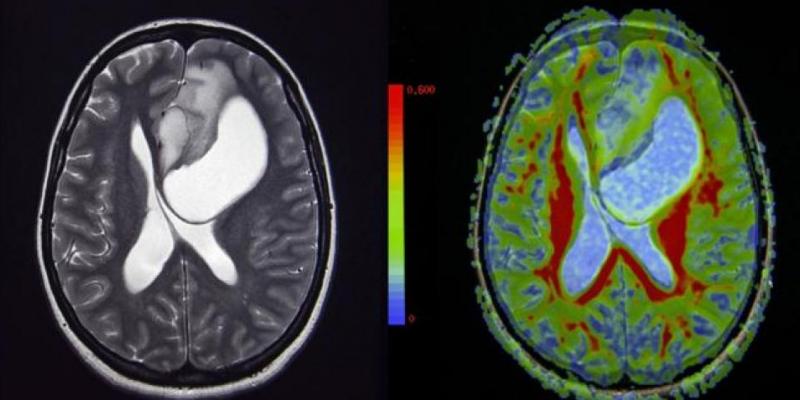

El glioma difuso intrínseco de tronco, o también conocido como DIPG, es el tumor cerebral más común en los niños, además del más letal, hasta ahora. Una investigación donde ha participado la Clínica Universidad de Navarra ha modificado un virus del catarro para destruir las células cancerosas de este tumor.

Sin embargo, una investigación donde ha participado la Clínica Universidad de Navarra ha modificado un virus del catarro con el objetivo de destruir a estas células cancerosas, y así ha sido. Gracias a este nuevo descubrimiento científico, las esperanzas de supervivencia ante este tipo de tumores son cada vez mayores.

El estudio clínico se inició en el 2017, hasta enero de 2020, con un total de 12 pacientes de entre 3 y 18 años, el cual logró aumentar la supervivencia de los participantes de los 12 meses a los 17,8 meses gracias al uso de un adenovirus, que se replica en células tumorales en pacientes con tumor cerebral recién diagnosticado.

Sin embargo, la estrategia demostró una gran efectividad, ya que nueve de los pacientes lograron reducir el tamaño del tumor cerebral, además de mostrar respuestas muy favorables. La supervivencia media se elevó a 17,8 meses.